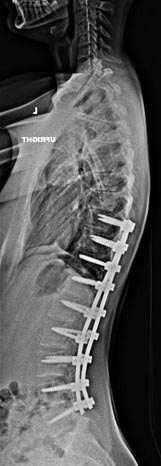

21 year old woman with very ridged 90 degree Scheuremann's kyphosis corrected to 40 degrees.